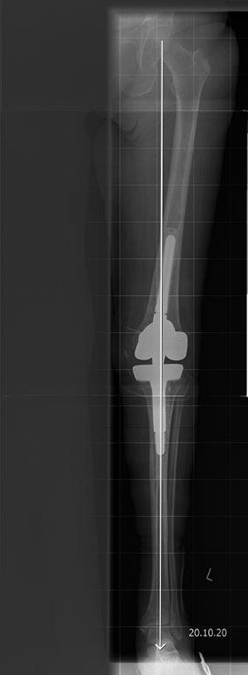

Zur Operation gehört bereits zuvor eine genaue Planung. Denn die Kunst in der Operation des künstlichen Kniegelenkes besteht darin, während des Eingriffs die oftmals stark veränderte Kniegelenksachse wieder weitgehend gerade auszurichten und eine stabile Beweglichkeit möglichst mit den eigenen Kniegelenksbändern wiederherzustellen. Hierbei werden zur individuellen Planung vor der Operation verschiedene standardisierte Röntgenaufnahmen angelegt, um den individuellen Knochenbau zu erfassen. Dabei besteht in unserer Klinik die Möglichkeit, den Gelenkersatz vor der Implantation individuell und passgenau am Computer zu simulieren. Dabei können auch besondere Situationen vorab genau analysiert werden, um auf diese während der Operation gezielt eingehen zu können.

Durch den Gelenkverschleiß und die damit einhergehenden Veränderungen ist oft die knöcherne Formgebung des Gelenkes zum Operationszeitpunkt deutlich verändert und eignet sich nur bedingt als Referenzpunkt für die Positionierung von Implantaten. Wir bevorzugen daher eine weichteilbalancierte Technik, die auf der Schienbeinkopfseite die Operation beginnt.

In einem zweiten stationären Aufenthalt, nachdem die Patientin wieder zu Kräften gekommen war, wurde dann im Oktober ein künstliches Kniegelenk eingesetzt. Die erhebliche Knochendefektsituation, sowohl auf der Oberschenkel als auch Unterschenkelseite, wurde durch ein spezielles Revisionsknie mit Ausgleich der knöchernen Defekte über Metallaufbauten bewerkstelligt. Die Patientin erholte sich weiter und arbeitet inzwischen wieder als Friseurin in Ihrem Salon.